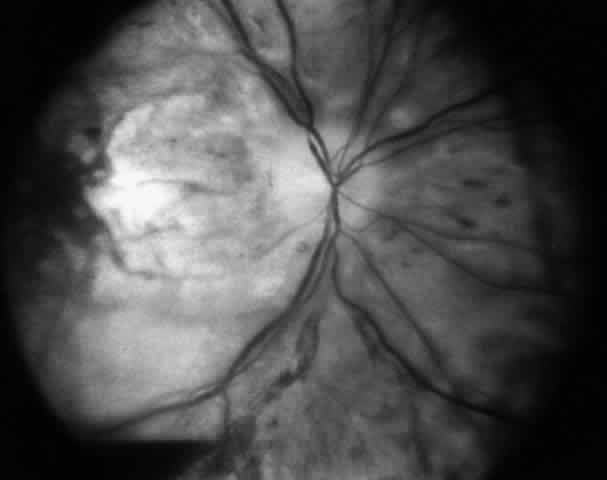

Absolute contraindications include any procedure that carries a significant risk of loss of vision. For example, if there is a significant risk of anterior segment ischemia, or if ischemia occurred in the patient previously, and alterations in surgical technique will not reduce this risk, surgery is inadvisable. If correction of a problem requires surgery on the sound eye of a patient with monocular blindness, and the patient cannot accept the remote risk of loss of vision, surgery is contraindicated (Fig. 6). Reoperation should not be attempted in situations wherein the surgeon is unable to understand the causes of the motility problem or is unable to formulate a surgical plan that has a reasonable chance for successfully achieving the desired alignment. Surgical risks and morbidity are also probably not justifiable in some cases where the patient has a very limited life expectancy. As for any surgery, unacceptable anesthetic risk is a strict contraindication to reoperation.

Fig. 6. Loss of vision after strabismus surgery is very uncommon. This 45-year-old woman had received orbital radiation prior to her strabismus surgery. The surgery was performed with retrobulbar anesthesia. Four days after the operation, vision was decreased from 20/20 to light perception. It is presumed that there was injection of the anesthetic into or around the optic nerve that caused compromise of the central retinal artery. The fundus photograph was taken 4 days after the procedure.

Loss of vision is uncommon after strabismus surgery. Excessive traction on rectus muscles may compromise blood supply to the globe. Patients who have had radiation to the orbit or extensive amounts of orbital surgery, from either repair of retinal detachment or multiple strabismus operations, are at greatest risk. If a procedure is performed under intravenous sedation combined with retrobulbar anesthesia, the restriction of the orbital contents due to excessive scarring may fixate the optic nerve, and the anesthetic may be injected into the optic nerve, causing optic nerve trauma (see Fig. 6). This can compromise the circulation of the central retinal artery. The use of a general anesthetic or performing the surgery with a perimuscular block will decrease the frequency of this very rare complication.